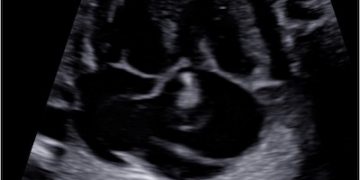

Cari soci, finalmente online le soluzioni dei casi del mese di Luglio Grazie a Carlotta Zorzi e Daniele Di Mascio!! Caso 1 - video [pdf-embedder url="https://www.sieog.it/wp-content/uploads/2024/07/risposta-Casodelmese_Luglio20241.pdf" title="risposta...